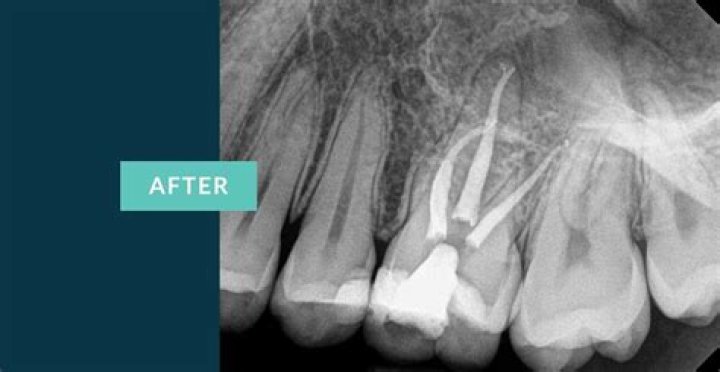

Before the procedure, your dentist will conduct a thorough examination, which may include X-rays to assess the extent of the damage. This helps determine the best approach for the root canal treatment.

Upper molars are particularly challenging due to their complex root structure. They often have three or four roots, each with its own canal, making the procedure more intricate than other teeth. Despite this complexity, modern techniques and technologies have significantly improved the success rate of upper molar root canals.

Upper molars are the largest teeth in the mouth and play a crucial role in grinding and chewing food. Their complex anatomy includes multiple roots, each housing a root canal. Typically, upper first molars have three roots, while upper second molars usually have two or three roots. This variation in root structure is one of the reasons why upper molar root canals can be more challenging than other teeth.

The complexity of upper molars lies in their root structure and location. The roots are often curved and can vary in length and diameter. This makes accessing and cleaning the canals more difficult. Additionally, upper molars are located further back in the mouth, making them harder to reach during treatment.